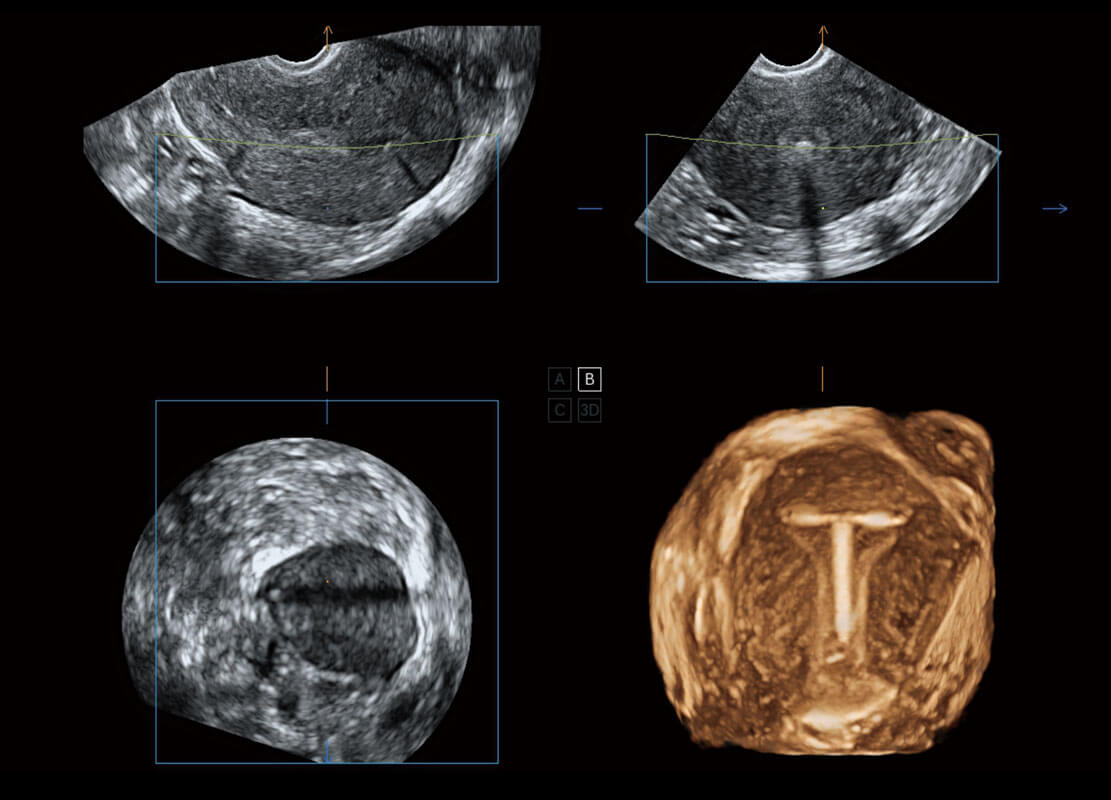

腔内妇科-卵巢

腔内三维-宫内节育器

腔内三维-光影成像